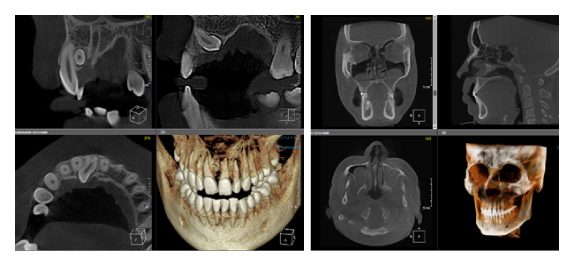

Когда мы отправляем пациента на проведение рентгенологического исследования, то подвергаем его определенному риску. Именно это нужно осознавать, так как в радиологии нет минимально безопасной дозы, поэтому любое назначение должно быть обоснованным. В связи с этим поле обзора является достаточно принципиальным параметром. Если вы врач-терапевт, занимающийся эндодонтией или ортопед, который решил оценить состояние зубов перед протезированием, то вы должны понимать, что проведение исследования с полем обзора 10x10 см будет гораздо информативнее нежели большие снимки (18x16 см и выше). В первую очередь это связано с размером вокселя, о нём я напишу чуть ниже, а второе это то, что вам придется увеличивать изображение по каждому корневому каналу, и от этого вы будете терять в качестве снимка (рис. 1). И ситуация наоборот, если вы ортодонт, то чтобы использовать весь диагностический потенциал, а также возможность загрузить данные для расчёта 3D цефалометрии, то вам нужны снимки, захватывающие весь лицевой отдел черепа. Таким образом, дентальный томограф должен обладать возможностью проведения исследований с разным FOV, обеспечивая нужды всех специалистов. Если ваша клиника базируется на терапевтическом, хирургическом и ортопедическом приёме, то на мой взгляд, можно рассмотреть дентальные томографы с полем обзора 10x10 см или 16x10 см. Последний больше актуален для тех, кто работает с ВНЧС, так как антропометрически в 16 см даже у брахицефалов сустав должен попадать. Если в клинике есть ортодонтическое направление, функциональная стоматология, ЛОР-практика или ЧЛХ, то, безусловно, вышепредставленные снимки не будут отражать всех данных, которые необходимы для диагностики и планирования лечения. Здесь лучше рассмотреть конусно-лучевые компьютерные томографы с зоной сканирования 18x16 или 20x20 см. Особо стоит отметить понятие «сшивки». Есть дентальные томографы, которые делают один цельный снимок размерами, которые описаны выше, а есть аппараты, которым нужно провести две экспозиции и сшить изображения вместе, чтобы получился необходимый объём исследования. Как правило, вторые томографы чуть дешевле, но всё зависит от того, насколько вам нужна максимальная точность исследования. Если при сшивке челюсти и зубы, как правило, совмещаются практически идеально, то на уровне позвоночного столба происходит наслоение тканей и от него уже не избавиться (рис. 2). Второй отрицательный момент – это износ оборудования, логично, что он будет быстрее, так что экономия средств — это ещё спорный вопрос.

Рис. 2. Левый снимок представлен исследованием 20x20 см единым изображением. Стрелками показаны чёткость канально-корневой системы зуба, а также позвоночника. Правый снимок представлен исследованием 16x15 см с функцией сшивки. Стрелками обозначены чёткость зуба, но двойной контур позвоночника.